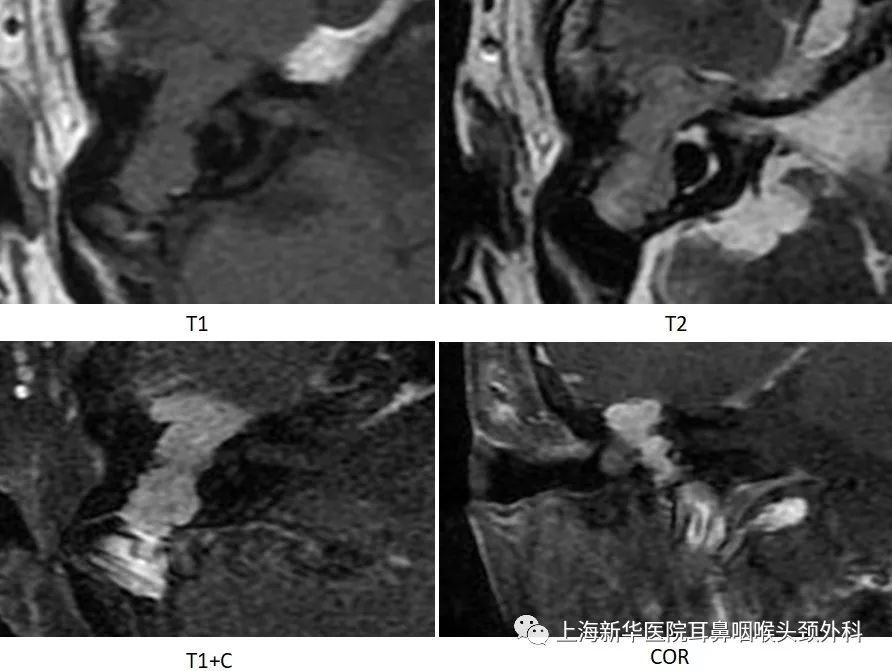

术后CT:

术后增强MRI: